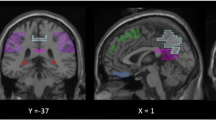

Cluster-based event-related potentials (ERP) and event-related spectral perturbations (ERSP). A and C ERP of the healthy- and the cognitively impaired (CI) group in each experimental night (E1, E2, and E3). Significant clusters in the ERP (p < 0.05) are shown as gray bars behind the curves. The second induced slow wave (SW) peak is highlighted in orange for visual inspection. B and D Significant ERSP clusters of the healthy and CI groups in each experimental night (E1, E2, and E3) vs. the baseline night (p < 0.01). Positive clusters are shown in red (i.e., increased activity in experimental vs. baseline night), and negative clusters are in blue (i.e., decreased activity in experimental vs. baseline night)

Electrophysiological response to PLAS: induced second slow-wave peak

Figure 3A and C shows the ERP of the baseline night (black line) and all experimental nights (red lines) with an induced trough around 0.5–1 s and, indeed, an induced second SW peak around 1–1.5 s after the stimulation (0 s) for the healthy group (Fig. 3A) and the CI group (Fig. 3C). The gray bars behind the curves in the ERPs of Fig. 3 show clusters of significant difference between experimental and baseline nights (p < 0.05). These time windows represent the electrophysiological response to PLAS. Visually, the electrophysiological response seems to get stronger (i.e., larger differences, wider and more numerous clusters of difference in gray) across the experimental nights in the CI group but stays stable over the three experimental nights in the healthy group. For a formalized analysis of this apparent development, see below (section “Delayed electrophysiological effect in CI group”).

Cluster-based significance testing of the ERSP in the experimental nights confirmed diverging patterns of the two groups: in the healthy group, there was a consistent, significant (p < 0.01) increase in power in the SW (~ 1 Hz), delta (1–4 Hz), and theta (4–8 Hz) ranges in all three experimental nights around the induced second SW peak (see Fig. 3B). In parallel, there was a consistent, but slightly shifted, decrease in theta and delta powers and an increase in spindle power (12–16 Hz) around the induced second SW peak as well as decreased beta power (12–16 Hz) in the pre-stimulus window. In the CI group, however, the magnitude of induced power changes seemed to increase across the three experimental nights in the same power frequencies (see Fig. 3D).